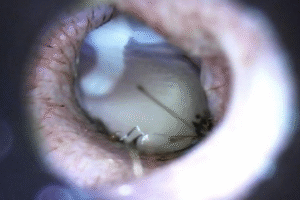

Video otoscopia

Video otoscopia

La video otoscopia è un ausilio diagnostico fondamentale nelle indagini del canale auricolare in corso di otiti e corpi estranei. Tramite questo strumento si rende possibile l’asportazione di materiale patologico all’interno dell’orecchio e l’esame completo del canale auricolare e del timpano.